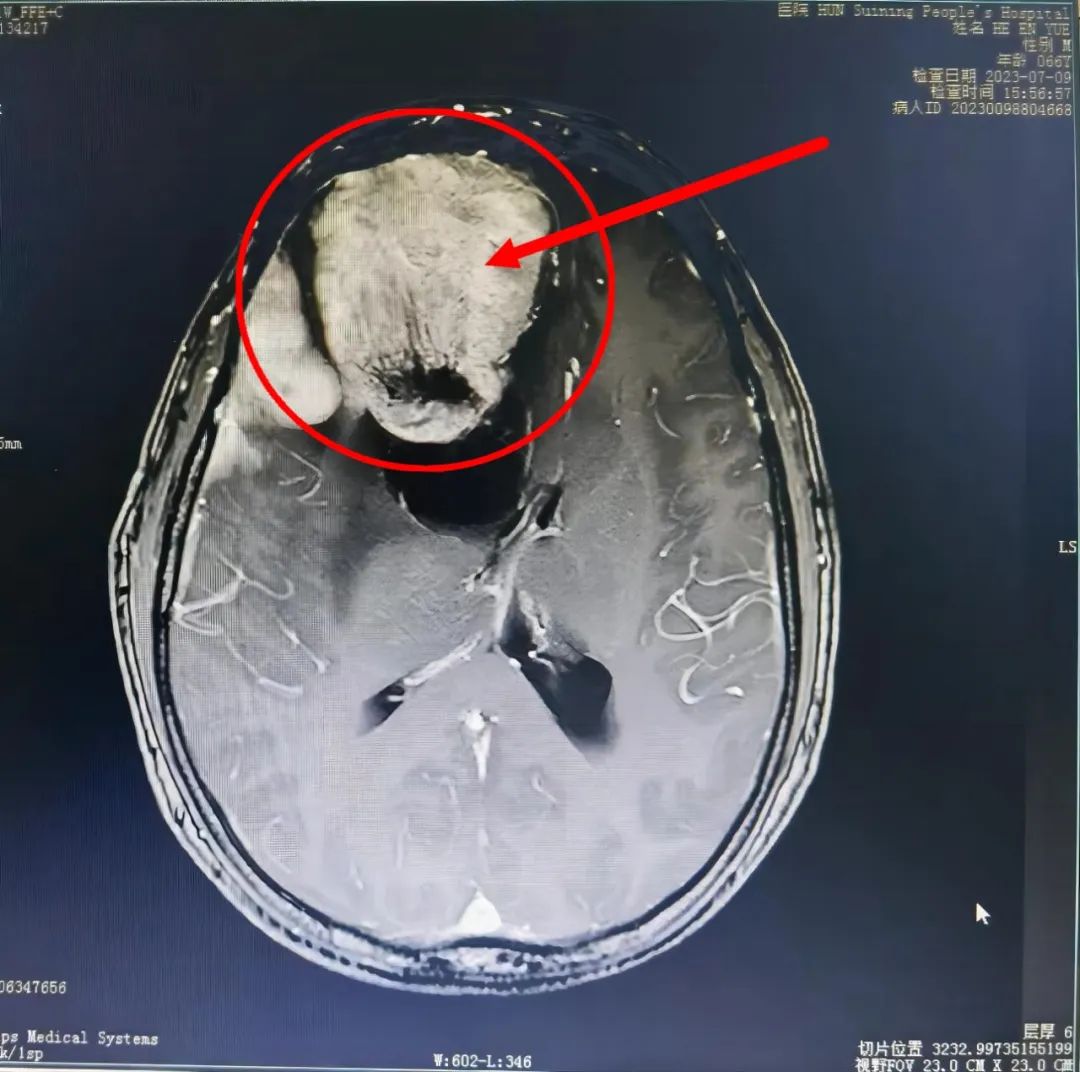

术前VS术后

术前VS术后 在廖新斌博士和黄敏主任的带领下,神经外科团队认真讨论并充分做好术前准备,如期为贺大爷实施了“前颅窝底复发肿瘤”切除术。手术效果及术后恢复良好,贺大爷于8月3日康复出院,并对科室团队的专业技术和卓越服务竖起了大拇指,其家属也送来锦旗表示感谢。